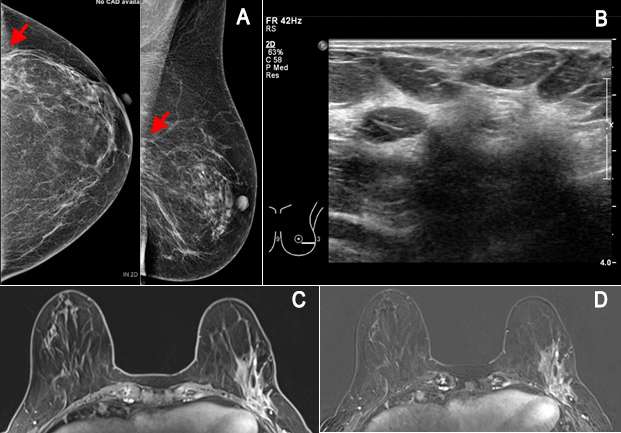

35-year-old female with biopsy proven invasive lobular carcinoma of the right breast underwent imaging for the evaluation of treatment response to neoadjuvant therapy.

Figure 3. 35-year-old female with biopsy proven invasive lobular carcinoma of the right breast underwent imaging for the evaluation of treatment response to neoadjuvant therapy. (A) Pre-therapy T1-weighted fat saturated post contrast imaging at 90 seconds showed an enhancing mass with a biopsy microclip at 12 o’clock, 5 cm from the nipple. (B) After 3 cycles of neoadjuvant chemotherapy, T1-weighted fat saturated post contrast imaging at the same time interval showed a biopsy microclip with no periclip enhancement in the region of previously seen mass at 12 o’clock. These findings demonstrate complete response to neoadjuvant therapy.